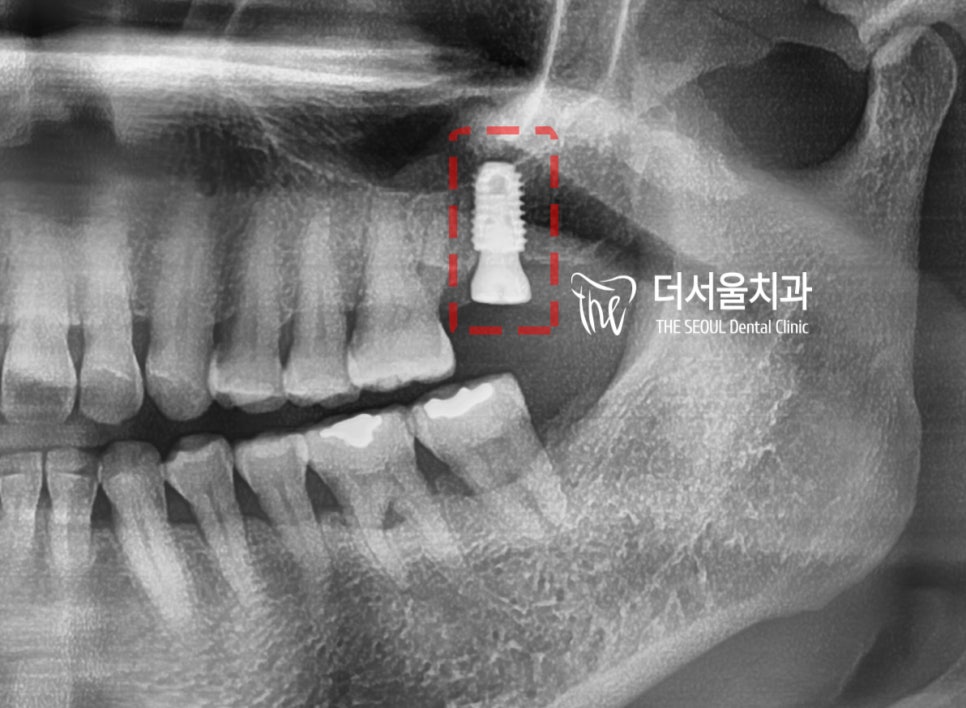

어금니 흔들림 이 있던 곳에는,

발치를 통해서 빈 공간이 되었고

상방에는 상악동 이라는 거시공간이

존재하고 있습니다.

근데, 심겨질 고정체의 apex 쪽이랑

겹쳐 예상치를 볼 수 있죠?

상악동거상술을 하지 않은 채,

그냥 시술을 진행했다가는 천공이

일어날 가능성이 농후합니다.

대략, 3~4mm 가량만 막을 거상하면

될 거 같네요.

시술을 해야 될 곳은, 범위가 크지 않기 때문에

creatal appraching 으로 진행됩니다.

(수직 거상법)

어금니 흔들림 위치에,

여러가지 술식이 병행되었으며

사전 진단 시뮬레이션 결과에 따라서

고정체가 심겨졌습니다.

이제 여기서, 뼈가 잘 아물면

지르코니아 크라운까지 시적해드리는데

큰 문제가 없습니다.